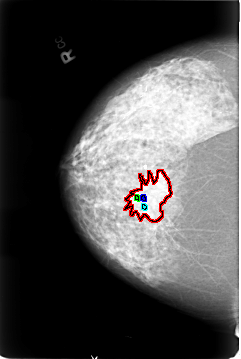

FILE: B_3026_1.RIGHT_MLO.OVERLAY

TOTAL_ABNORMALITIES 4

ABNORMALITY 1

LESION_TYPE MASS SHAPE IRREGULAR-ARCHITECTURAL_DISTORTION MARGINS OBSCURED-ILL_DEFINED-SPICULATED

ASSESSMENT 4

SUBTLETY 3

PATHOLOGY MALIGNANT

ABNORMALITY 2

LESION_TYPE CALCIFICATION TYPE PLEOMORPHIC DISTRIBUTION CLUSTERED

ABNORMALITY 3

ABNORMALITY 4